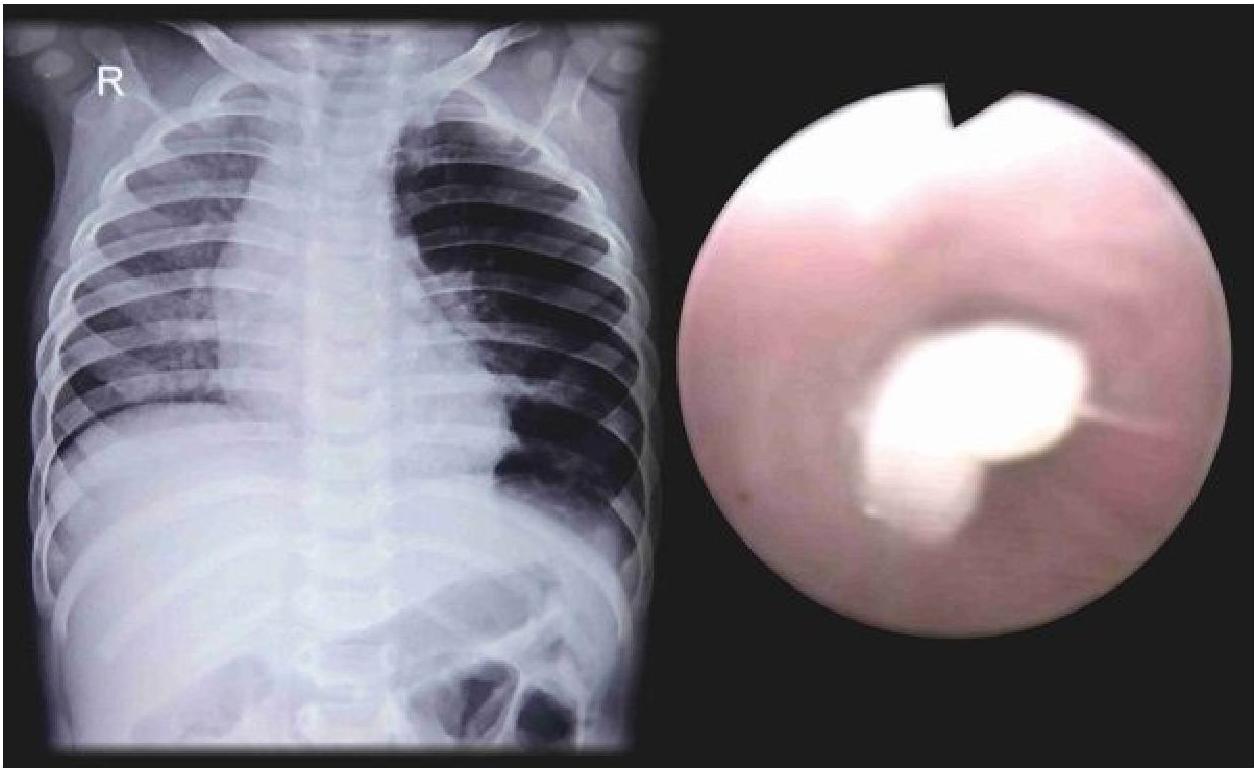

- Bronchial FBA Findings in chest x-ray:

- Hyperinflated lung

- Atelectasis

- Mediastinal shift

- Pneumonia

Left: Focal pneumonia in lower right lung lobe due to aspiration and airway obstruction. Right: Coin in the esophagus.

Foreign body aspiration of a coin in the esophagus